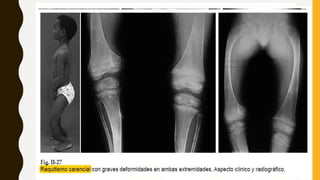

TRATAMIENTO QX